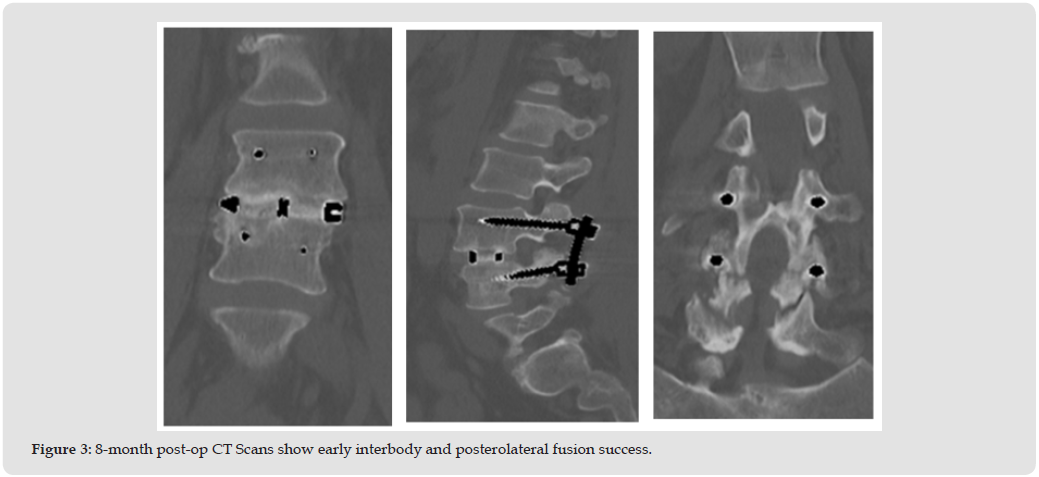

At the 3-month follow-up radiographs showed the instrumentation intact and in good position (Figure 2). Clinically the patients’ pain symptoms had improved dramatically (VAS Back-1.4/10, VAS Right Leg-0.4/10, VAS Left Leg-0.9/10, ODI -50%) and the patient continued physical therapy. CT scans were obtained at the next follow- up (8.2 months) due to a moderate increase in pain symptoms (VAS Back-6.0/10, VAS Right Leg-7.6/10, VAS Left Leg-1.0/10, ODI- 34%) as a result of increased activity and reduction of pain medication however the ODI had improved to moderate disability. The CT scans exhibited early and complete interbody and posterolateral fusion success (Figure 3). By the 1-year follow-up the symptoms had mostly resolved with minor residual back pain and complete resolution of radicular pain (VAS Back-2.0/10, VAS Right Leg-0/10, VAS Left Leg-0/10, ODI-26%) with a clinically significant improvement of 22 points from pre-op in the ODI. CT Scans taken at 1 year confirm complete fusion in both the interbody and posterolateral constructs seen previously (Figure 4).